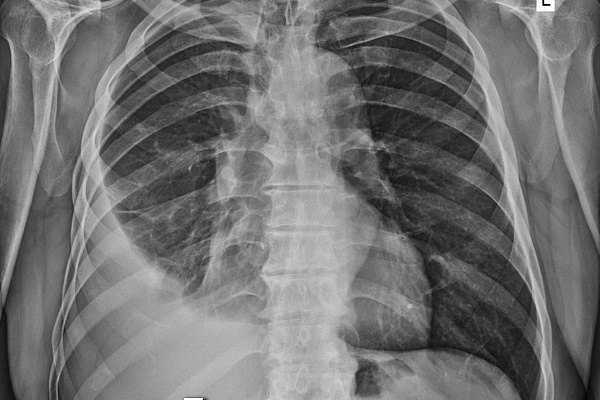

Правда, ситуации разные. Если с экрана нам рассказывают о последствиях травмы грудной клетки, то врачи травмбольницы имеют дело с грозным заболеванием, при котором плевральная полость заполняется гнойным содержимым. Из-за этого лёгкое сдавливается и не может полноценно участвовать в дыхательном процессе. Больные испытывают постоянную дыхательную недостаточность, у них развивается системная воспалительная реакция, интоксикационный синдром, в худшем случае – сепсис и полиорганная недостаточность.

Эмпиема плевры – вторичная патология, возникает как осложнение, в том числе, после вирусных и бактериальных пневмоний. За последние два года торакальные хирурги Сургутской травмбольницы внедрили и поставили на поток высокотехнологичную малоинвазивную методику оперативного лечения этого заболевания. Она пришла на смену тяжелым обширным вмешательствам на грудной клетке с длительным и сложным послеоперационным ведением больных.

Торакоскопическая методика кропотливая и технически непростая. Через три разреза от 0,5 до 1 сантиметра хирурги специальным инструментом разрушают и удаляют всю патологическую ткань – гнойные полости, спайки, шварты, фибринозные наложения. Двигаться необходимо очень осторожно, чтобы не повредить лёгкое. Работа проводится при повышенной из-за воспаления кровоточивости, а на отдельных участках кратно усложняется множеством тонких и уязвимых сосудов.